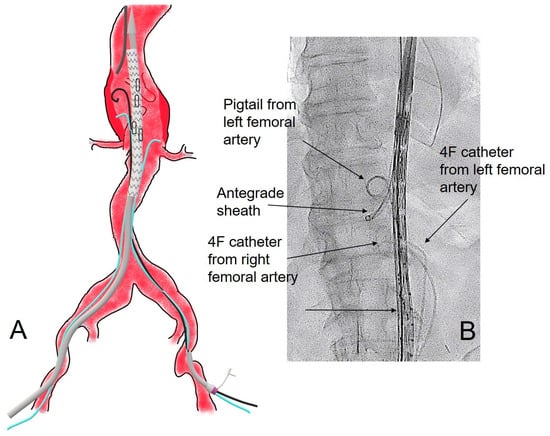

Experience of Alternative Technique for Branch Cannulation in Branched Endovascular Aneurysm Repair

Background/Objectives: To describe our experience of using an alternative technique for retrograde branch graft cannulation during Branched EndoVascular Aortic Repair (B-EVAR) of complex abdominal and thoraco-abdominal aortic aneurysm (TAAA) with branched endografts. Methods: Data from patients who underwent B-EVAR for TAAA/complex

Background/Objectives: To describe our experience of using an alternative technique for retrograde branch graft cannulation during Branched EndoVascular Aortic Repair (B-EVAR) of complex abdominal and thoraco-abdominal aortic aneurysm (TAAA) with branched endografts. Methods: Data from patients who underwent B-EVAR for TAAA/complex abdominal aneurysms and in whom the cannulation of a branch was performed through a retrograde approach with our technique were retrospectively collected and analyzed. The technique consists of the placement of two 4F Ber catheters in both femoral arteries, which are advanced in parallel with the main graft before its deployment and left in the aneurysmal sac. These catheters are then used as a bailout for the retrograde cannulation of one or more branches of the endograft. Results: The technique was employed in 4 patients (1 female, 1 urgent) treated from 2018 onward, allowing the successful catheterization of 4 challenging branches that could not be catheterized using other approaches. The patients’ mean age was 80.7 + 2.2 years. No intraoperative nor postoperative complications linked to the technique occurred. Conclusions: The placement of two catheters from both femoral arteries inside the aneurysmal sac before graft deployment can be safe and useful for bailout retrograde cannulation of any branch of the endograft, when other techniques fail.